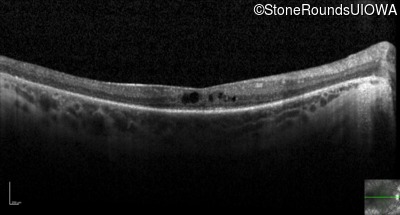

Optical Coherence Tomography - Left - 20/70 +1

Exemplar / OCT Stack